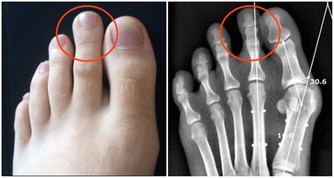

而維持適當的體重則有助於預防這些疾病,進而延長壽命。此外,體重過重或肥胖也會對身體造成額外的負擔,例如會導致關節炎、骨質疏鬆等疾病的發生。